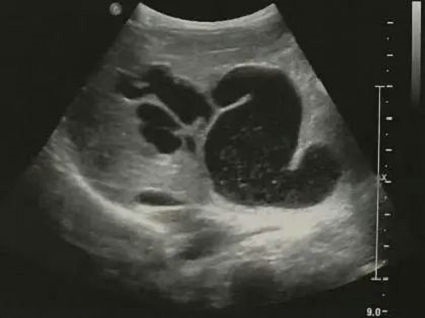

胆道闭锁患儿生后即出现黄疸、进行性加重、皮肤巩膜黄染、面色暗黄、大便淡黄色或白色陶土样等症状。由于新生儿胆总管纤细难以观察,因此通过以下胆囊形态变化判断是否胆道梗阻:胆囊大小正常但形态僵硬(图2),边缘不光整,长度可达2-3cm,内径大于0.4cm,可有小的憩室样结构形成;小胆囊,长度小于1-1.5cm,内径0.2cm,充盈差;胆囊小而且无充盈,仅可见胆囊痕迹,喂奶后无变化;以上三种胆囊均可合并有胆总管区囊肿,可与胆囊管及胆囊相通,但与肝左、右管不相通(见图3);小部分病例可见到肝内胆管局限性扩张(图4);病程后期(3个月以上),显示肝硬化改变(图5)。

▲ 图2 ▲ 图3